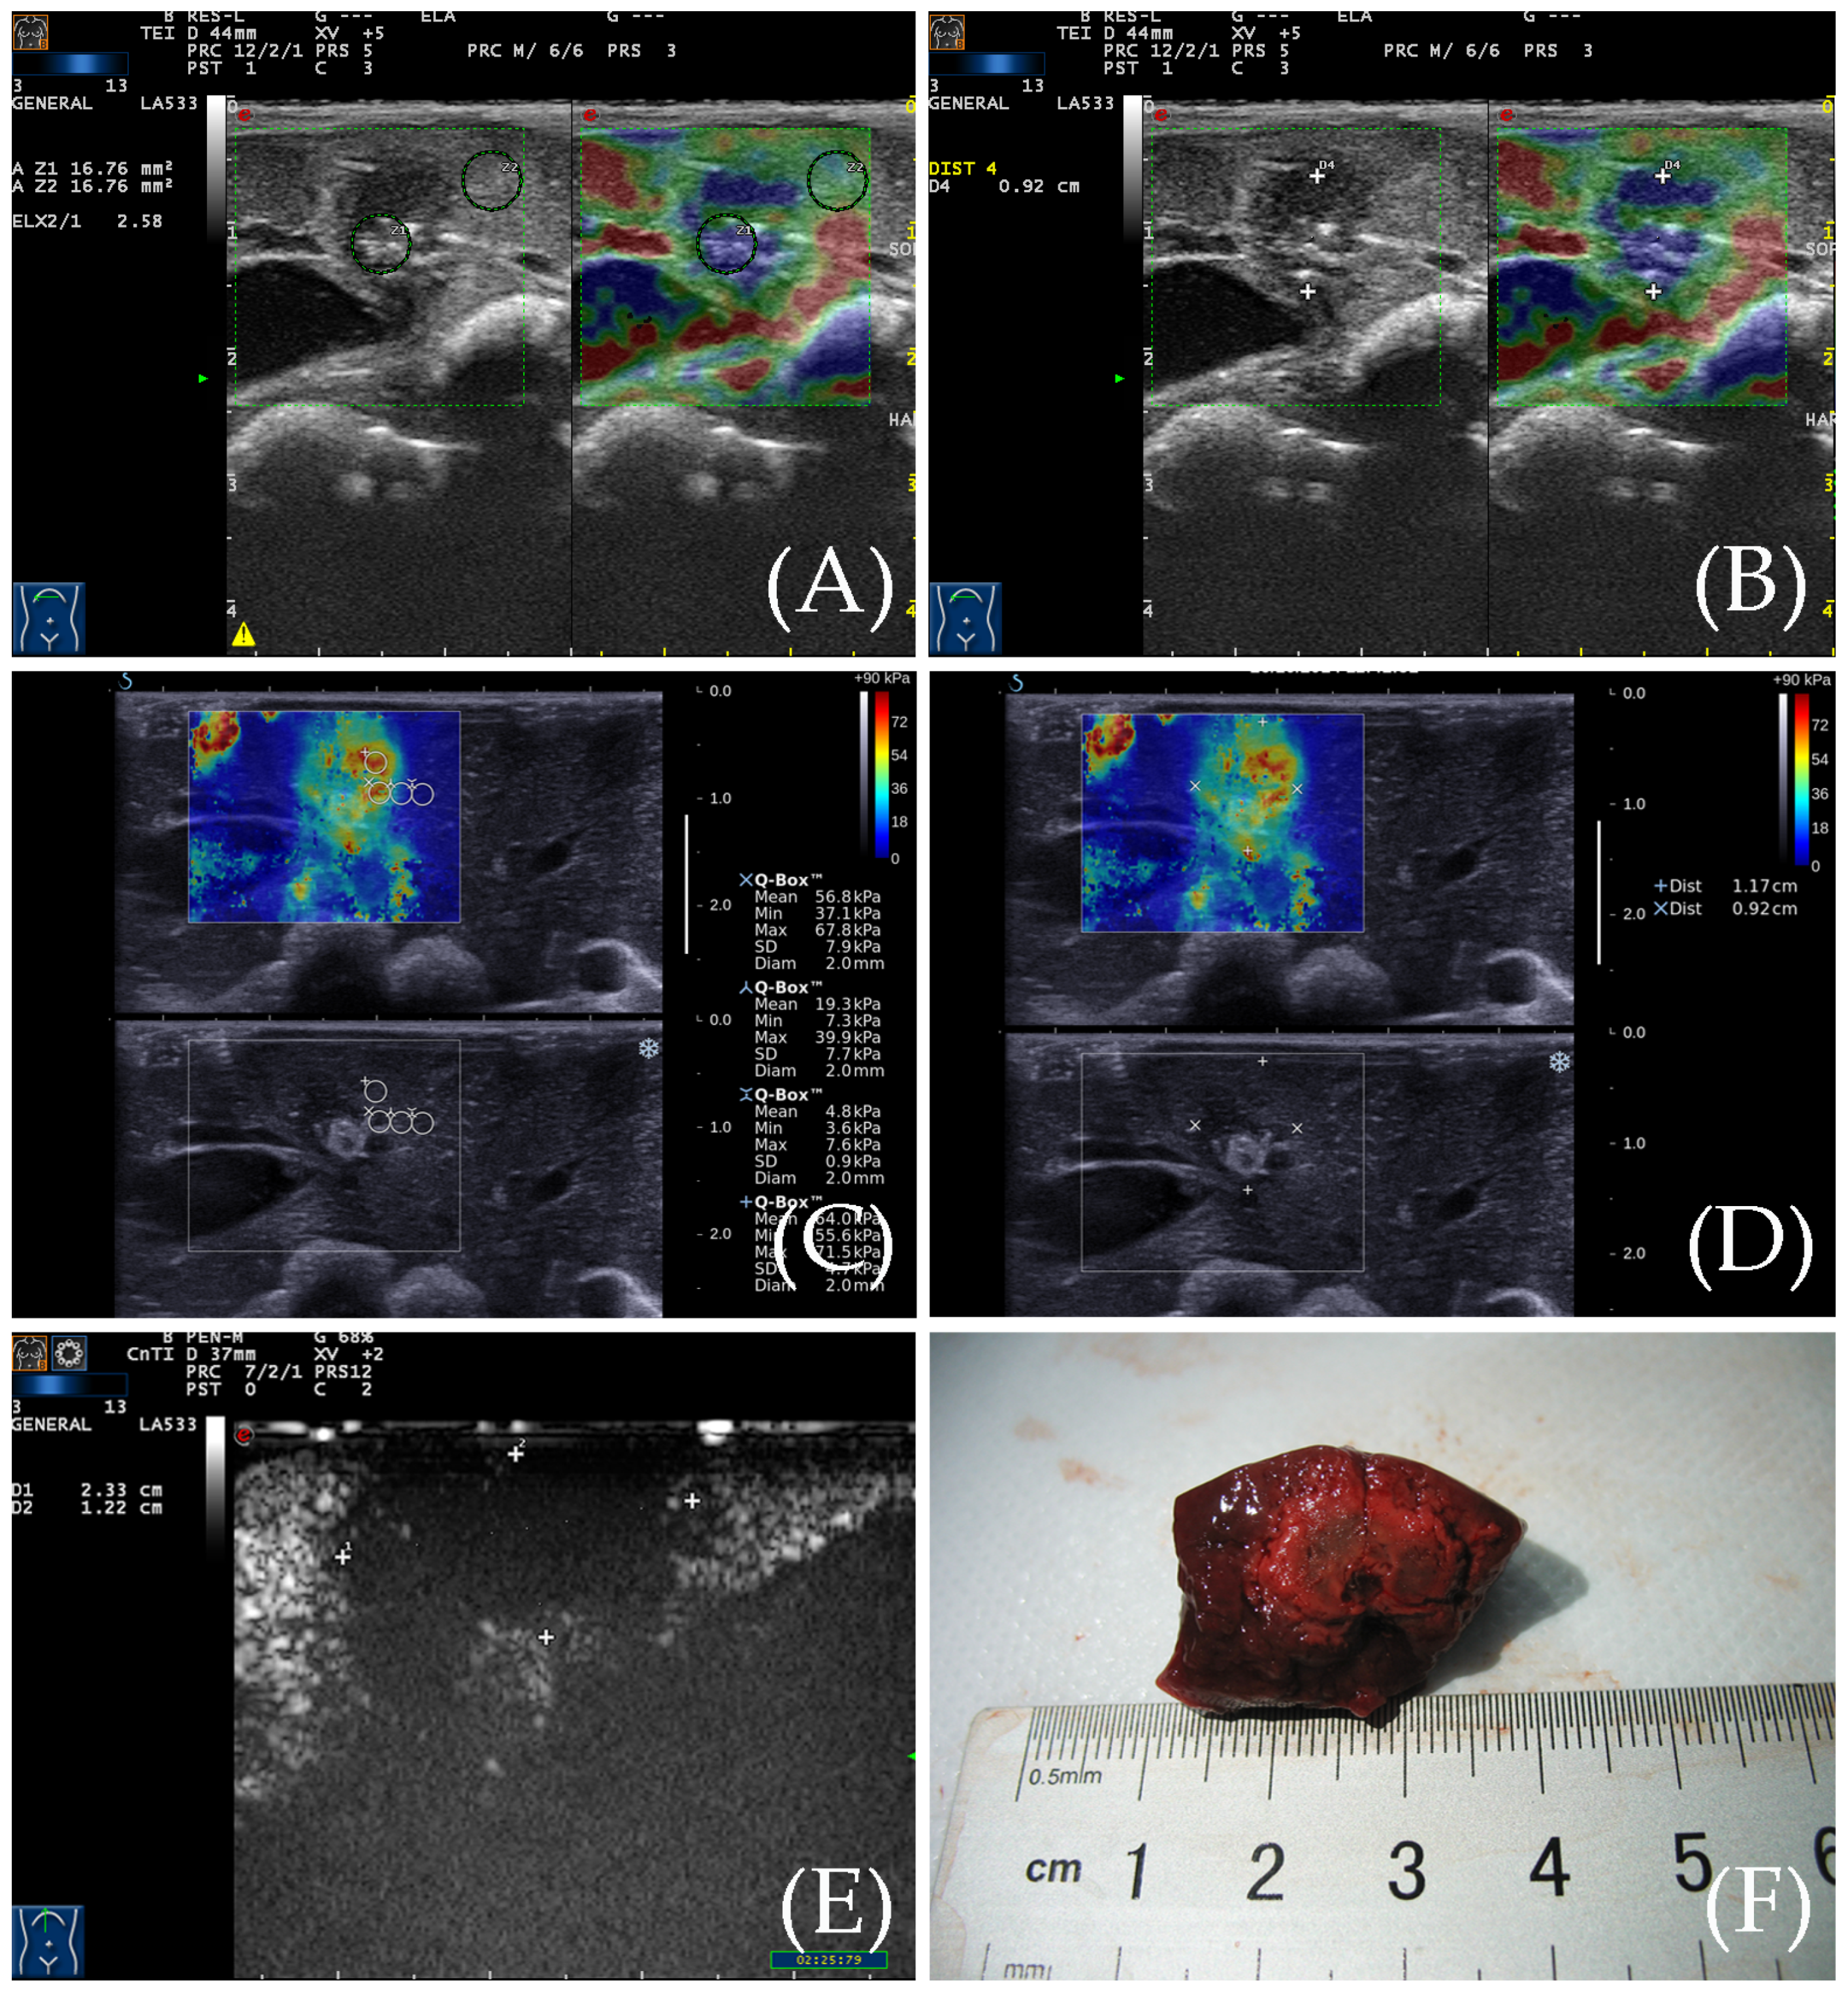

3.1. The Situation of the Ablation Zone

3.2. RTE for the Detection of the Ablation Zone

3.3. SWE for the Detection of the Ablation Zone

3.4. Contrast-Enhanced Ultrasound Examination

3.5. Gross Specimen Observation and Comparison of the Three Imaging Methods